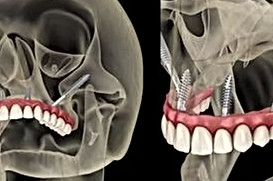

Zygomatic implants are a game-changer for patients with severe bone loss, but mastering this advanced technique requires specialized training. With so many courses available globally, choosing the right one can be challenging.